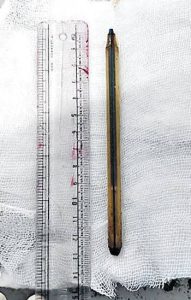

వైద్యులు సీటీ స్కాన్ చేయగా, మురళీకృష్ణ పెద్దపేగులో పెన్ను ఇరుక్కున్నట్లు నిర్ధారించారు. గ్యాస్ట్రో ఎంటరాలజీ విభాగాధిపతి డాక్టర్ కవిత ఆధ్వర్యంలో అసోసియేట్ ప్రొఫెసర్ నాగూర్ బాషా, అసిస్టెంట్ ప్రొఫెసర్ శివరామకృష్ణల బృందం రెట్రోగ్రేడ్ ఎంటెరోస్కోపీ విత్ ఓవర్ ట్యూబ్ పద్ధతితో శస్త్రచికిత్స అవసరం లేకుండానే పెన్నును విజయవంతంగా బయటకు తీశారు.

ఈ అరుదైన శస్త్రచికిత్స లేకుండా చేసిన చికిత్సతో బాలుడి ప్రాణాలను కాపాడగలిగామని ఆసుపత్రి సూపరింటెండెంట్ రమణ విలేకరుల సమావేశంలో తెలిపారు. వైద్యుల బృందాన్ని ఆయన అభినందించారు. పిల్లలు పందెం పేరుతో ఇలాంటి ప్రమాదకర చర్యలకు పాల్పడకుండా తల్లిదండ్రులు అప్రమత్తంగా ఉండాలని వైద్యులు సూచించారు.